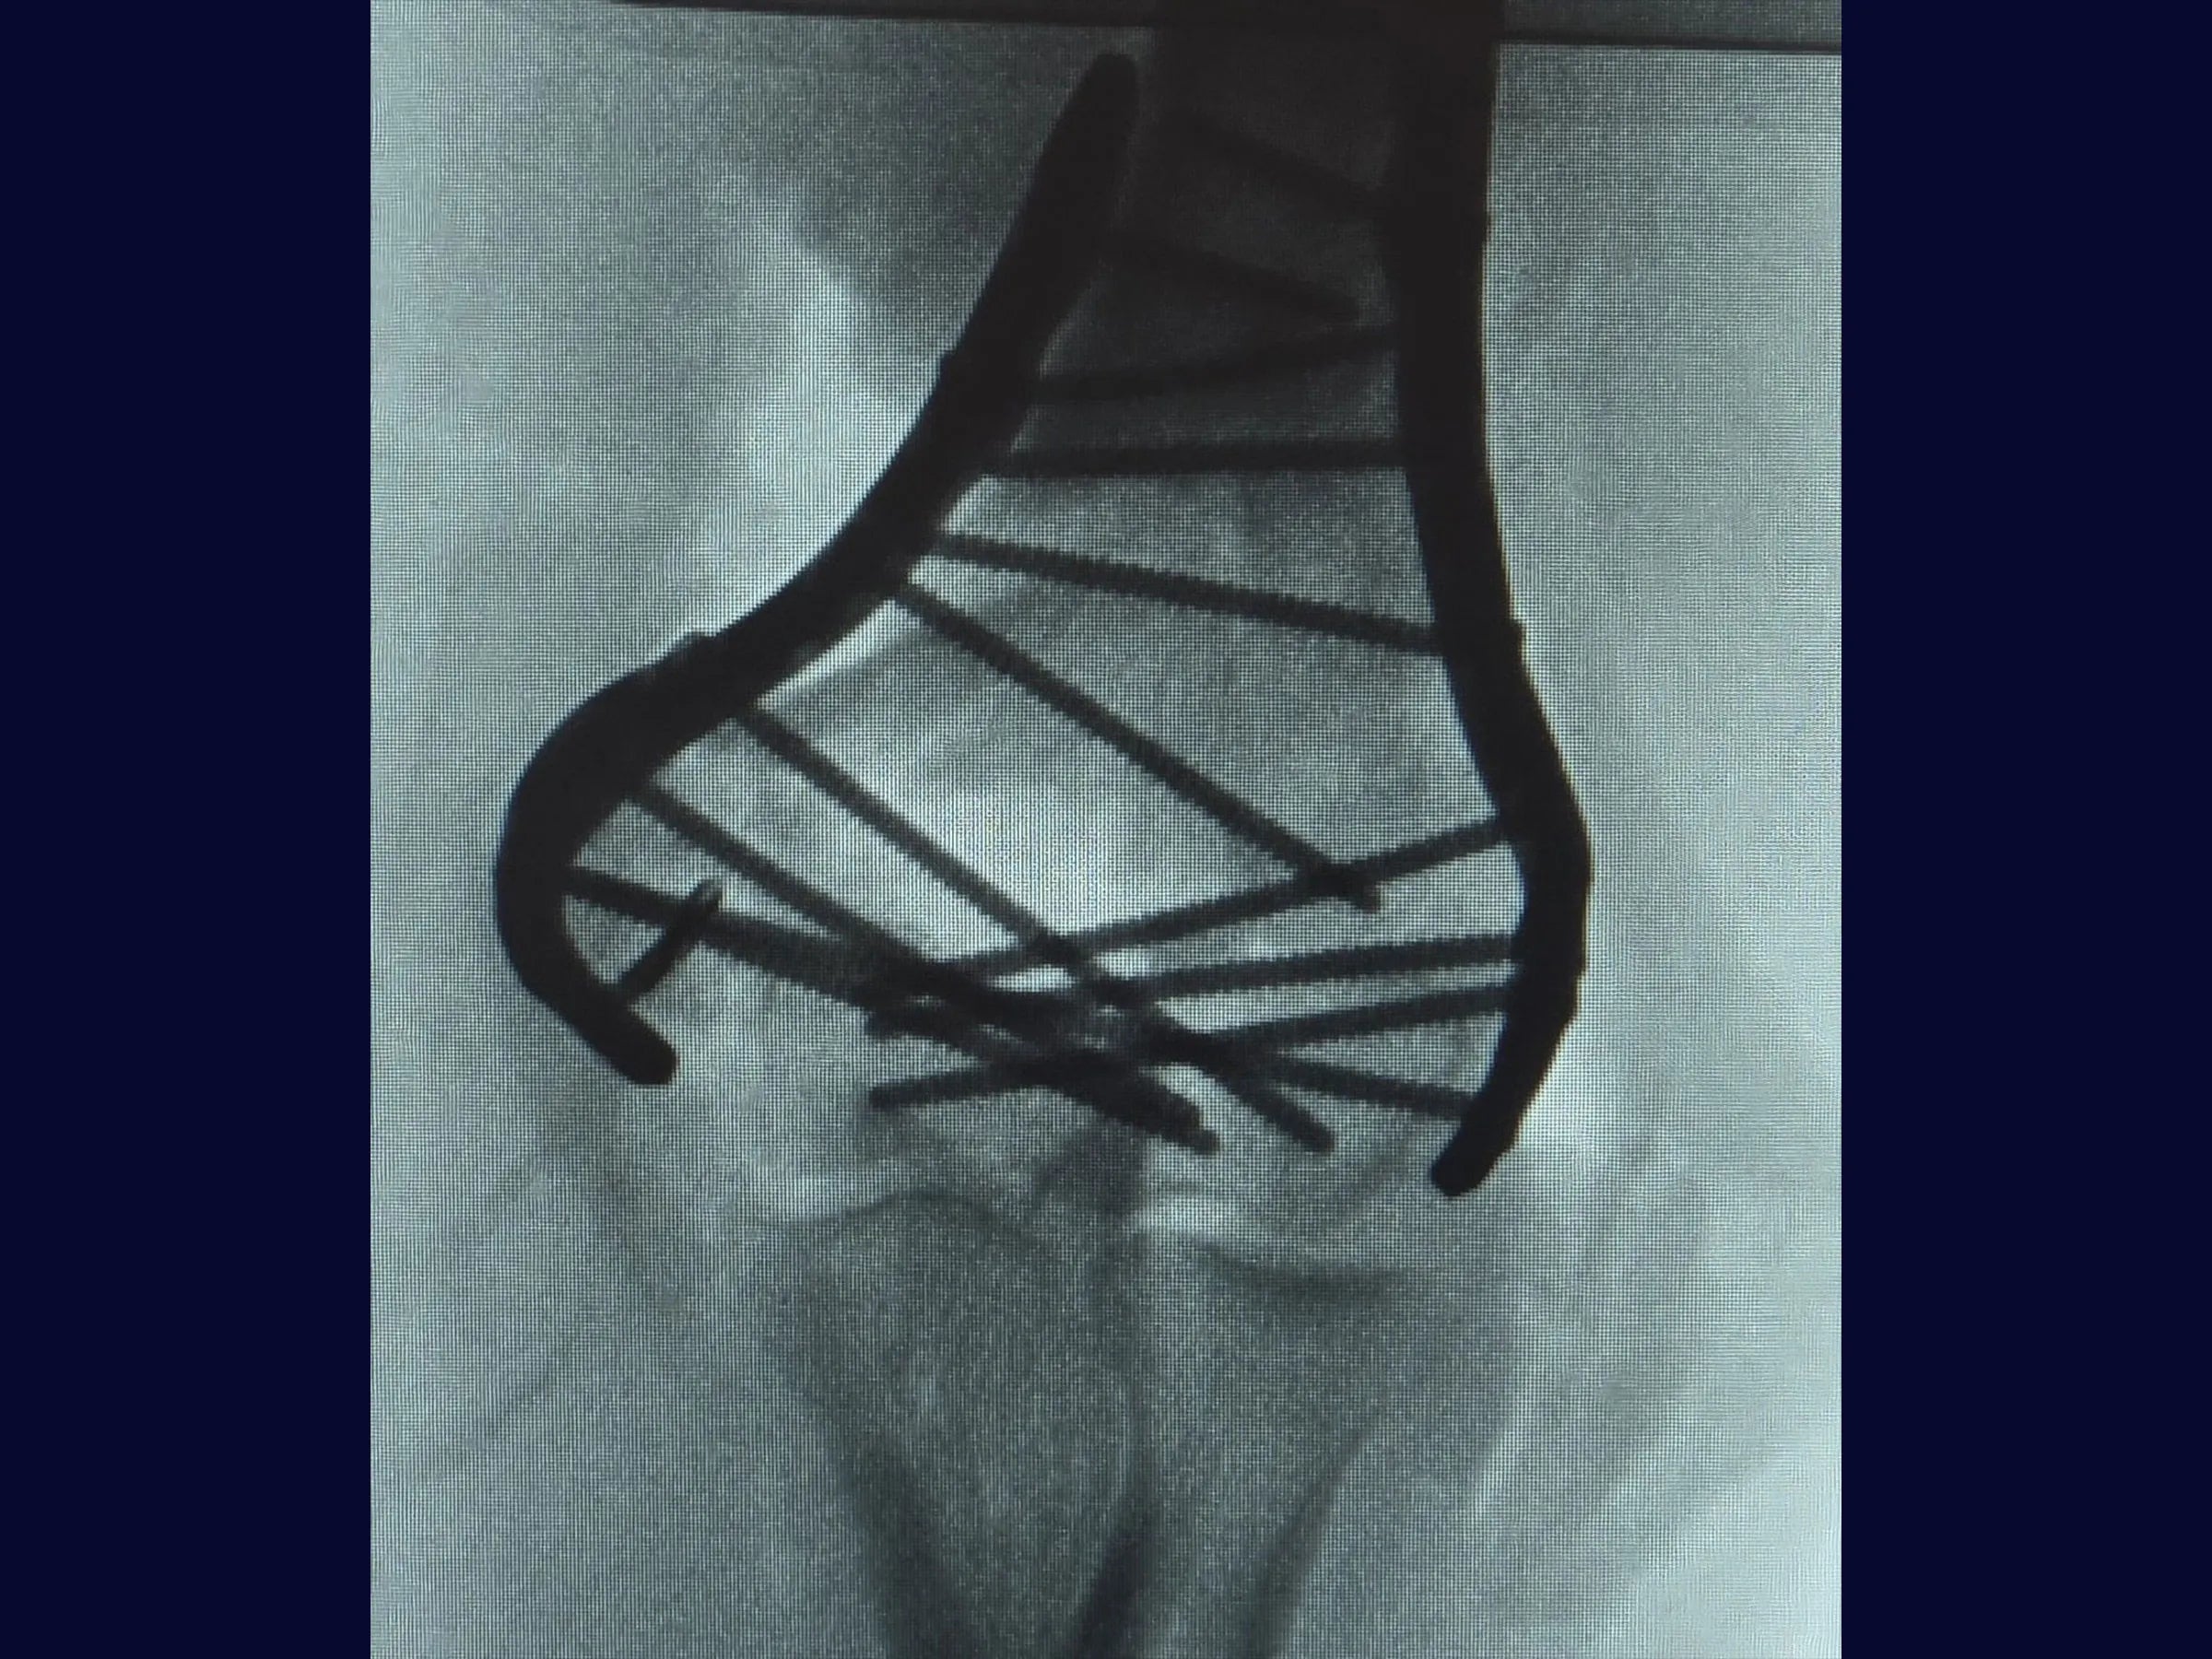

As fraturas articulares multifragmentares do úmero distal representam um dos maiores desafios na cirurgia do trauma, exigindo precisão na redução articular e estabilidade que permita mobilização precoce.

Este treinamento oferece uma visão detalhada da fixação rígida com placas de ângulo variável, apresentada em vídeo 4K sob a perspectiva cirúrgica, com comentários técnicos e material complementar em PDF.

- Osteotomia em Chevron no olécrano para ampla exposição articular.

- Redução de fragmentos articulares com fios de Kirschner em joystick.

- Fixação definitiva com placas bloqueadas de ângulo variável.

- Redução Controlada: Uso de fios K como joystick para manipulação de fragmentos articulares e restauração das colunas.

- Fixação Estável: Aplicação de placas bloqueadas de ângulo variável para alinhamento seguro e resistência biomecânica.